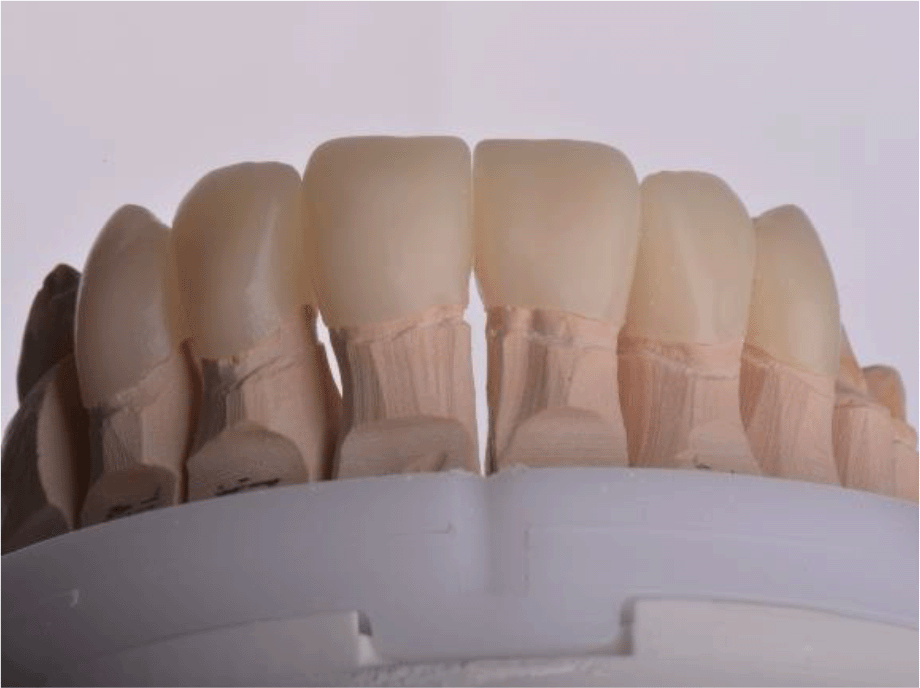

For the adaptation period, it was preferred that the temporary construction of the upper jaw be made of PMMA (Ceramill TempML), which was cemented with temporary cement (Prevision (Kulzer)). This construction was intended to remain in the patient’s mouth throughout the period of adaptation and, if necessary, to be optimized (Figures 11 and 12).

Figure 11. PMMA crowns on a model.

Figure 12. PMMA crowns cemented in the mount.